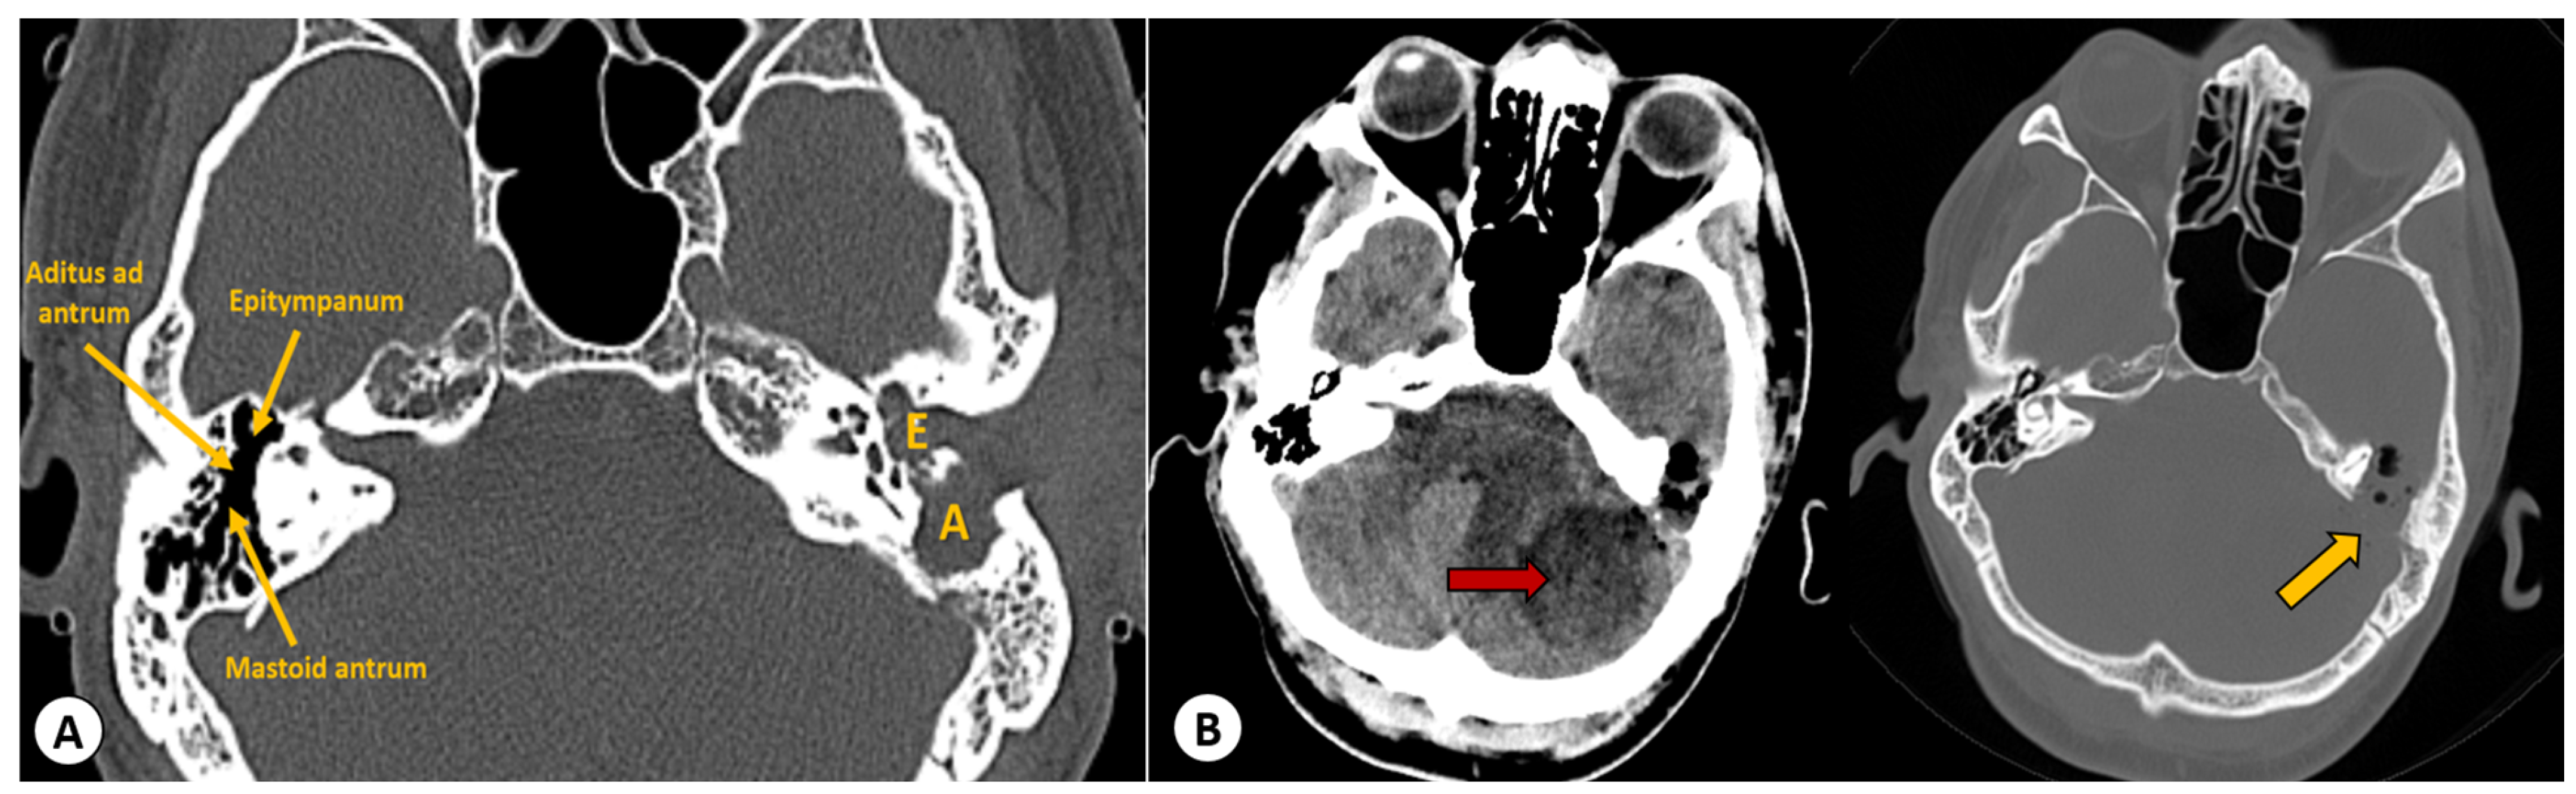

An emergency surgical intervention was performed, involving the evacuation of the cerebellar abscess through a left suboccipital craniectomy. A follow-up CT scan of the head showed successful evacuation of the abscess, but the communication between the mastoid and the intracranial space remained (Figure 5).

ENT procedures were performed on the third day, once the patient’s condition had stabilized. The purpose of the surgery was to remove the cholesteatoma, the underlying cause of the complications. After creating a retroauricular incision, the mastoid was drilled (Figure 6). At this point, pus was observed coming from the exposed extradural space, and it was aspirated using suction. Subsequently, the antrum was uncovered, which was found to be occupied by a large, infected cholesteatoma, extending into the aditus, attic, and intersinuso-facial cells, and towards the apex of the mastoid. The cholesteatoma was carefully removed, and it necessitated a canal wall down procedure. Granulation tissue and the cholesteatoma were also removed from the mastoid, and purulent secretions were aspirated from the tympanic cavity. During the surgery, we observed that the wall of the facial canal was mildly eroded by the cholesteatoma.

In the end, we examined the cells and antrum, and removed all the lesions under the microscope until only healthy bone tissue remained. The dural and bony defect in the posterior fossa was then sealed with a free muscle graft harvested from the occipitalis muscle, and the adherence was achieved using surgical adhesive glue (Figure 7).

In the end, a large cavity remained, which we utilized for draining the remaining pus. Cultures of the pus from the mastoid process and cerebellar abscess were sterile, likely due to the patient’s prolonged antibiotic therapy. The patient was monitored with head CT scans at 2 and 6 months, and after 30 days of antibiotics, we observed the closure of the bony defect through which the cholesteatoma cavity communicated with the posterior fossa (Figure 8).

Figure 6. Head CT imaging 3D reconstructions highlighting the left antrostomy: (A) External view of the left auricular region, showing the communication made with the cholesteatoma cavity (white asterisk): 1—zygomatic arch, 2—ramus of mandible, 3—mastoid process, 4—styloid process. (B) Skull base with 1—petrous bone, 2—internal auditory meatus, 3—petroclival fissure, 4—clivus, 5—posterior fossa. White asterisk represents the communication made with the cholesteatoma cavity.